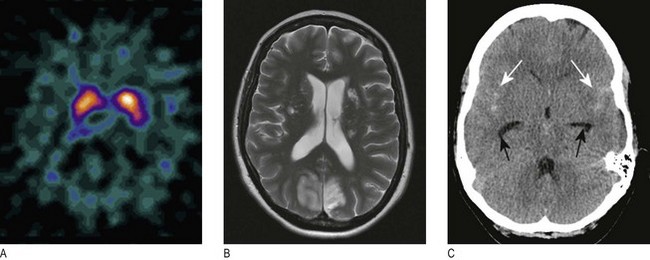

Fig. 11.33 Scanning of the head:

(A) DaTSCAN scan showing the distribution of blood flow on cross-section of the brain. (B) MR scan showing ischaemic stroke T2 imaging demonstrates bilateral occipital infarction and bilateral hemisphere lacunar infarction. (C) Unenhanced CT scan showing subarachnoid blood in both sylvian fissures (white arrows) and early hydrocephalus, with temporal horns of the lateral ventricles visible (black arrows).